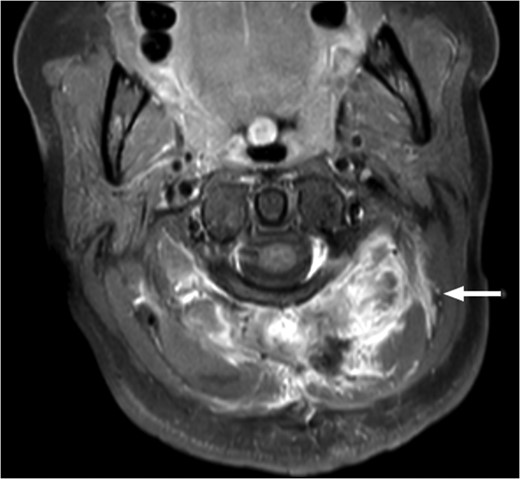

T1-weighted MRI showing the lesion eroding through the left basioccipital skull, impinging the dura overlying the left cerebellum.